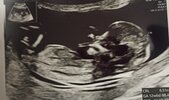

Dziewczyny, jestem po pierwszych prenatalnych (z pappa i plgf) i wszystko jest idealnie ❤️ tym razem doktorek nie zalecał badań genetycznych. Nie zdawałam sobie sprawy, jak bardzo byłam zablokowana obawami, że teraz coś będzie nie tak.

Lekarz mega pochwalił młodego (tak, "z dużą dozą prawdopodobieństwa" chłopiec teraz będzie 💙) za współpracę i mnie za super widoczność! Byłam w szoku, bo ja nie z tych chudych, raczej taka szczupła/ średnia.

Łożysko na tylnej ścianie macicy, więc super w kontekście mojego wcześniejszego cc.

• IMG_20230309_120424.jpg

IMG_20230309_120424.jpg

820,6 KB · Wyświetleń: 66